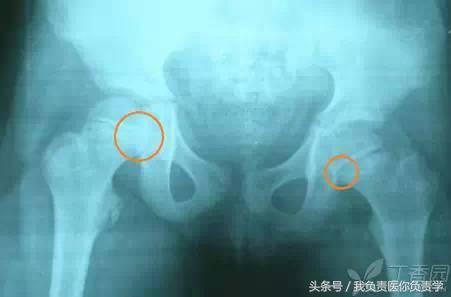

4. Straddle 骨折(骑跨损伤)

指累积双侧耻骨上下支或双侧耻坐骨支的骨折,常合并尿道损伤,有时骨盆后环也受到波及,常规行 CT 检查。